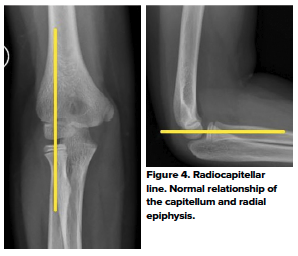

The anterior humeral and radiocapitellar lines are used to assess elbow alignment. The lines assess the geometric relationship of one bone to the other. Malalignment usually indicates fractures.

The radiocapitellar line evaluates the relationship of the proximal radius to the capitellum on all views (Fig 4). If the integrity of this line is compromised, then dislocation should be suspected (Fig 5)